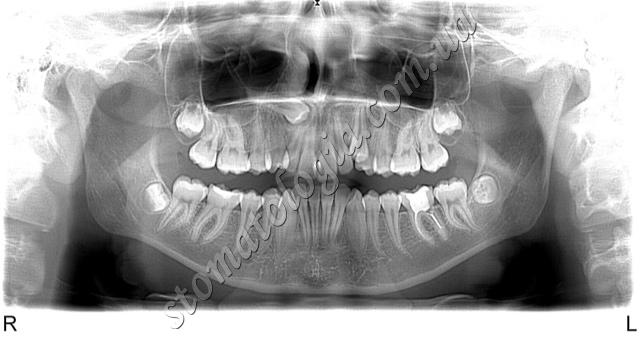

Ретиновані зуби: усі зуби мудрості (4 зуба) та ікла верхньої щелепи. Ретиновані й дистоповані зуби часто не можна побачити під час візуального огляду, але їх добре видно на КТ і рентгені